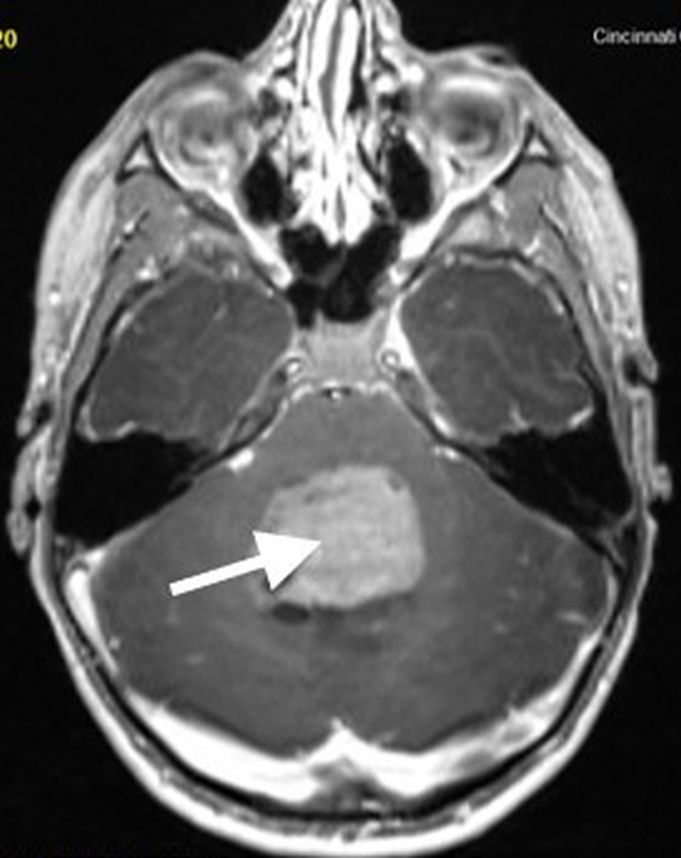

Imaging characteristics for the various subtypes of medulloblastoma are overall similar, reflecting that of densely packed, highly cellular tumors. Masses tend to be spherical in shape and displace adjacent structures, as opposed to the more pliable appearance of ependymomas. Increased density on CT and diffusion restriction on MRI are characteristic of medulloblastomas, reflective of their high cellularity. T2 signal intensity is variable, typically having areas of both increased and decreased T2 signal compared to cerebellar parenchyma. Small intralesional cysts are common, while intralesional hemorrhage and calcification are uncommon, though may occasionally be seen. Enhancement ranges from patchy to more robust solid enhancement [7, 8] (Fig. 1).